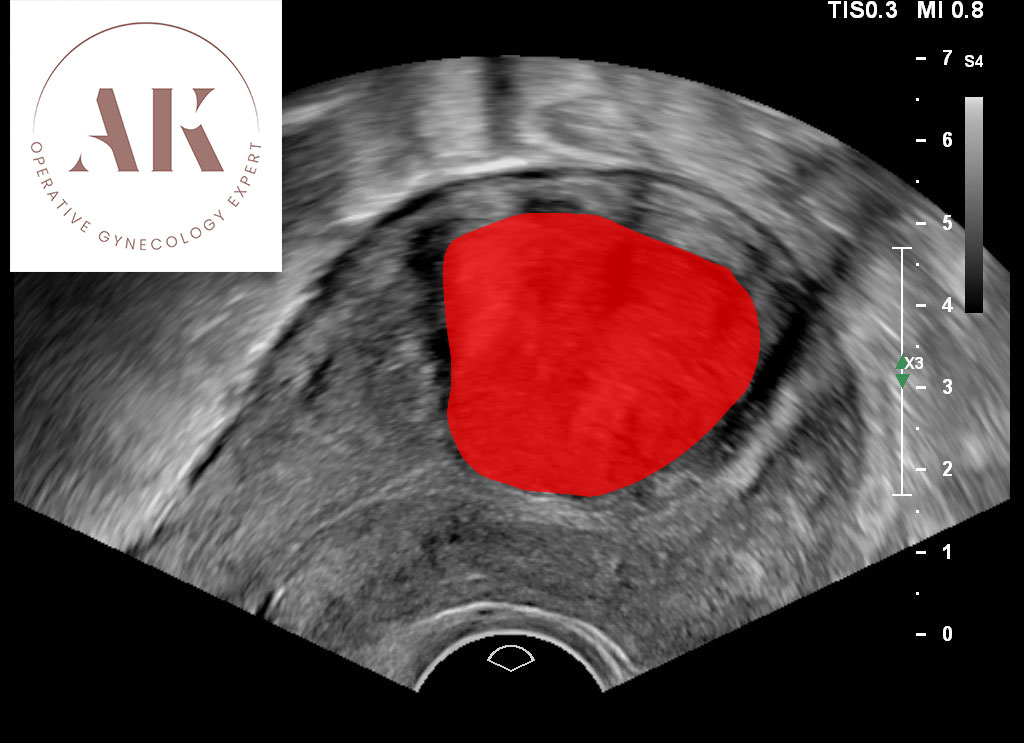

Τα ινομυώματα είναι καλοήθεις όγκοι που αναπτύσσονται από το μυϊκό τοίχωμα της μήτρας. Μπορεί να είναι μικρά ή μεγάλα, μοναδικά ή πολλαπλά και να αναπτύσσονται αργά ή γρήγορα. Είναι πάρα πολύ συχνά, καθώς υπολογίζεται ότι περίπου 1 στις 2 γυναίκες μέχρι την ηλικία των 50 ετών θα εμφανίσει κάποιο ινομύωμα.

Τα μικρά ή μεσαία ινομυώματα που βρίσκονται μακριά από την κοιλότητα της μήτρας συχνά δεν χρειάζονται θεραπεία. Η μεγάλη πλειοψηφία των ινομυωμάτων δεν προκαλούν προβλήματα. Ο καλύτερος τρόπος για να γνωρίζετε αν κάποιο ινομύωμα είναι ακίνδυνο ή όχι, είναι να προβείτε στη λεγόμενη χαρτογράφηση ινομυωμάτων (πατήστε εδώ για να μάθετε περισσότερα σχετικά με τη χαρτογράφηση ινομυωμάτων).